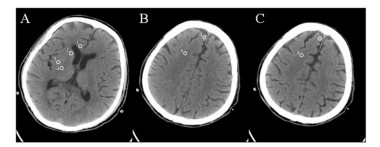

1.2 方法根据既往研究确定的方法[9-10],由两位研究者分别对患者CT图像进行分析,分别选择基底节、半卵圆中心及高凸性三个层面,采用圆形 (10 mm2) 测量方式,在双侧目的区域选取图像并进行CT值 (HU) 的测定。在基底节水平分别记录尾状核 (CN)、壳核 (PU)、胼胝体膝部 (CC) 及内囊后肢 (PIC) 的CT值,在半卵圆中心和高凸性水平分别记录灰质 (MC) 和白质 (MWM) CT值,并取双侧平均值,见图 1。GWR的计算方法具体为:GWR-基底节= (CN+PU)/(CC+ PIC),GWR-大脑=(MC1+MC2)/(MWM1+MWM2),GWR-平均=(GWR-BG+GWR-CO)/2,GWR-简化=PU/PIC[5, 10]。以患者出院时CPC评分作为临床预后判断的依据,CPC 1或2分为预后良好,CPC 3~5分为预后不良。

| 基底节水平 (A):1为胼胝体膝部,2为尾状核,3为壳核,4为内囊后肢;半卵圆中心 (B) 和高凸性水平 (C):5、7为灰质,6、8为白质 图 1 头颅CT双侧圆形目的区域的选择 Figure 1 Circular regions of interest were placed bilaterally on brain computed tomography |